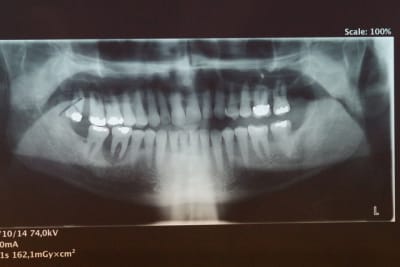

Le patient de 65 ans n'a plus d'occlusion sur le secteur ant et sur le secteur postérieur gauche.

L'occlusion ne se fait que sur les 5, 6 et 7 côté droit.

De ce fait la surcharge occlusale sur la 46 a entraîné une lyse osseuse importante qui contre indique la conservation de cette dent.

Cette lyse est sans doute aggravée par une hygiène très incertaine .

PS1 La ccm sur 26 a été réalisée en occlusion en 2005

J'entends par là que ce monsieur a l'ATM gauche luxée, probablement depuis un bout de temps. J'imagine que ça se verrait à la pano si les ATM étaient dans le cadre.

Concernant une radio des ATM, mon centre de radio m'a précisé que cela ne se faisait plus car la SS ne remboursait plus !!

Ils veulent faire une pano centré sur les ATM.

Je pense la faire faire afin d'éliminer définitivement une luxation de la mandibule.

Une pano montrant les ATM permettra de confirmer ou non la théorie de la luxation mandibulaire: plus de doutes possibles. L'IRM permettra d'écarter un autre problème ATM (luxation du disque), qui serait cependant bien étonnante au vu des symptômes.

Je pense aussi qu une pano bouche fermée et une en bouche ouverte serait intéressante pour savoir s il y a une luxation.

> Une pano montrant les ATM

SANS LA CALE INCISIVE : EN OCCLUSION!! ça te permettra de voir la place de tes condyles dans les cavités glénoïdes en occlusion. Si la luxation est permanente tu la verras.

Je vais faire faire au patient ces prochains jours une pano centrée sur les ATM bouche fermée.